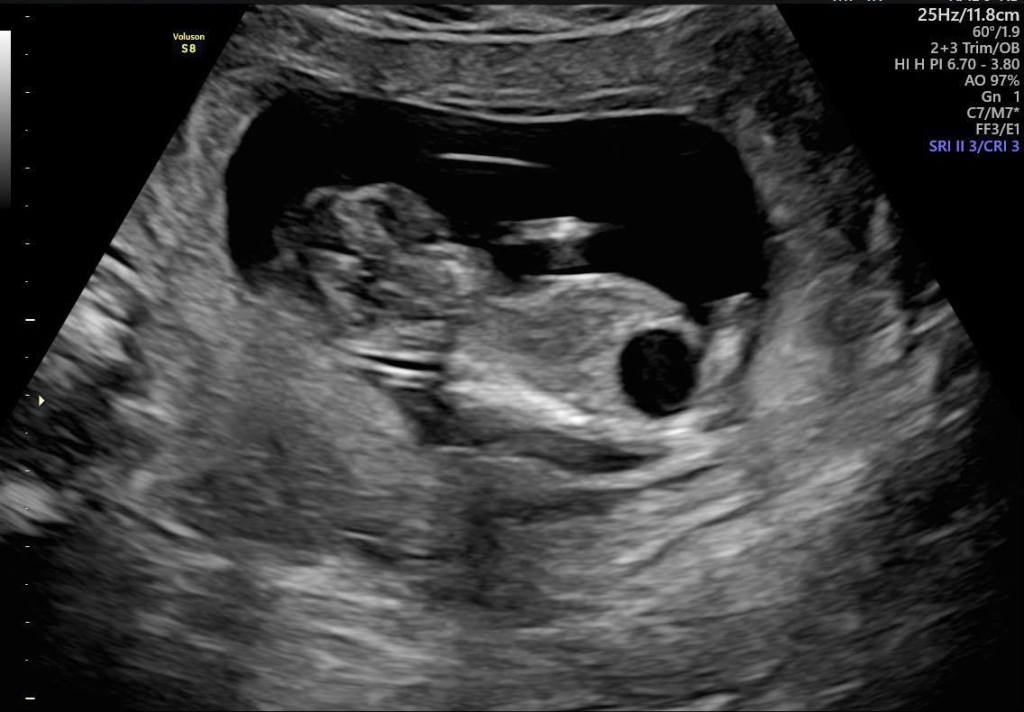

胎兒巨膀胱

我們要穿過媽媽的肚皮還有子宮還有羊水腔

然後把這根管子放到寶寶的膀胱跟羊水腔中間硬殺出一條通路